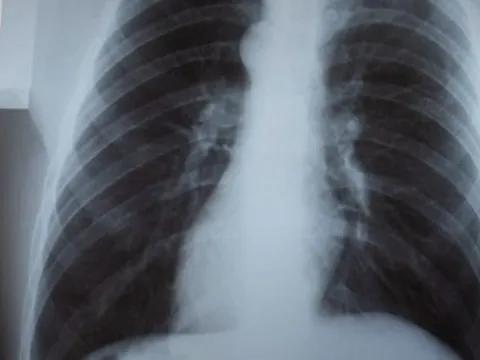

Trung Quốc giải thích hiện tượng trẻ em ốm tăng đột biến

Cơ quan y tế Trung Quốc cho biết, nhiều mầm bệnh khác nhau cùng hoành hành là nguyên nhân gây ra tình trạng gia tăng các bệnh về đường hô hấp cấp tính ở trẻ em, khiến khoa nhi trên khắp cả nước rơi vào tình trạng quá tải.

Thái Lan sẵn sàng các phương án đối phó với khả năng bùng dịch hô hấp ở trẻ

Bộ Y tế Công cộng Thái Lan đang nhanh chóng triển khai các biện pháp phòng ngừa để đối phó với căn bệnh hô hấp đang lây lan nhanh ở trẻ em tại miền Bắc Trung Quốc.